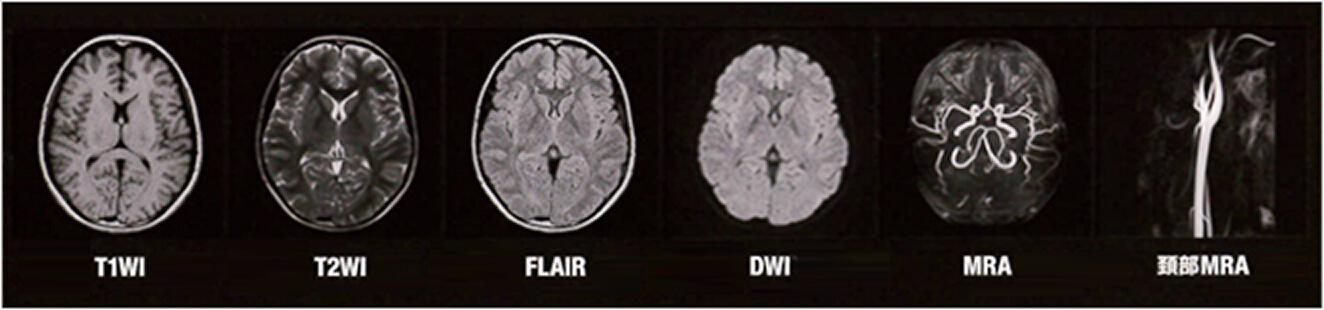

1.5テスラMRI装置を導入しました

高性能な1.5テスラMRI装置を導入しております。従来の約半分の時間でも、撮影画像はより鮮明で細かいところまで撮ることが可能な新技術を搭載しております。MRIは、磁石と電波を使って体の様々な断面像を撮像するので、放射線による被爆はありません。

また、造影剤を使用せずに血管の画像を得ることもでき、短時間で全身の検査も可能で患者様の負担が少なくなりました。くわしい検査内容は、医師またはスタッフまでお気軽にお尋ねください。

ルーチン検査を短時間で行うことが可能な機器を導入しております。また、通常のルーチンに、微小出血の描出を行うFSBB検査を組み込むことができるため、短い時間で高い臨床価値を実現しております。